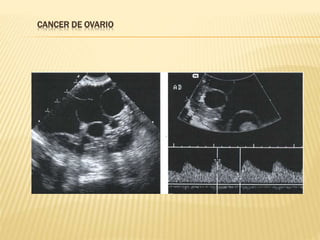

NEOPLASIA MALIGNA DE OVARIO

 CARACTERISTICAS ECOGRAFICAS

GENERALES

 Masas sólidas o quística con componente sólido

 Capsula con perdida de la continuidad

 Frecuentemente bilaterales

 Imágenes endo o exofiticas

 Tabiques con vasularización

 Flujo doppler con baja resistencia

 Ascitis

CANCER DE OVARIO